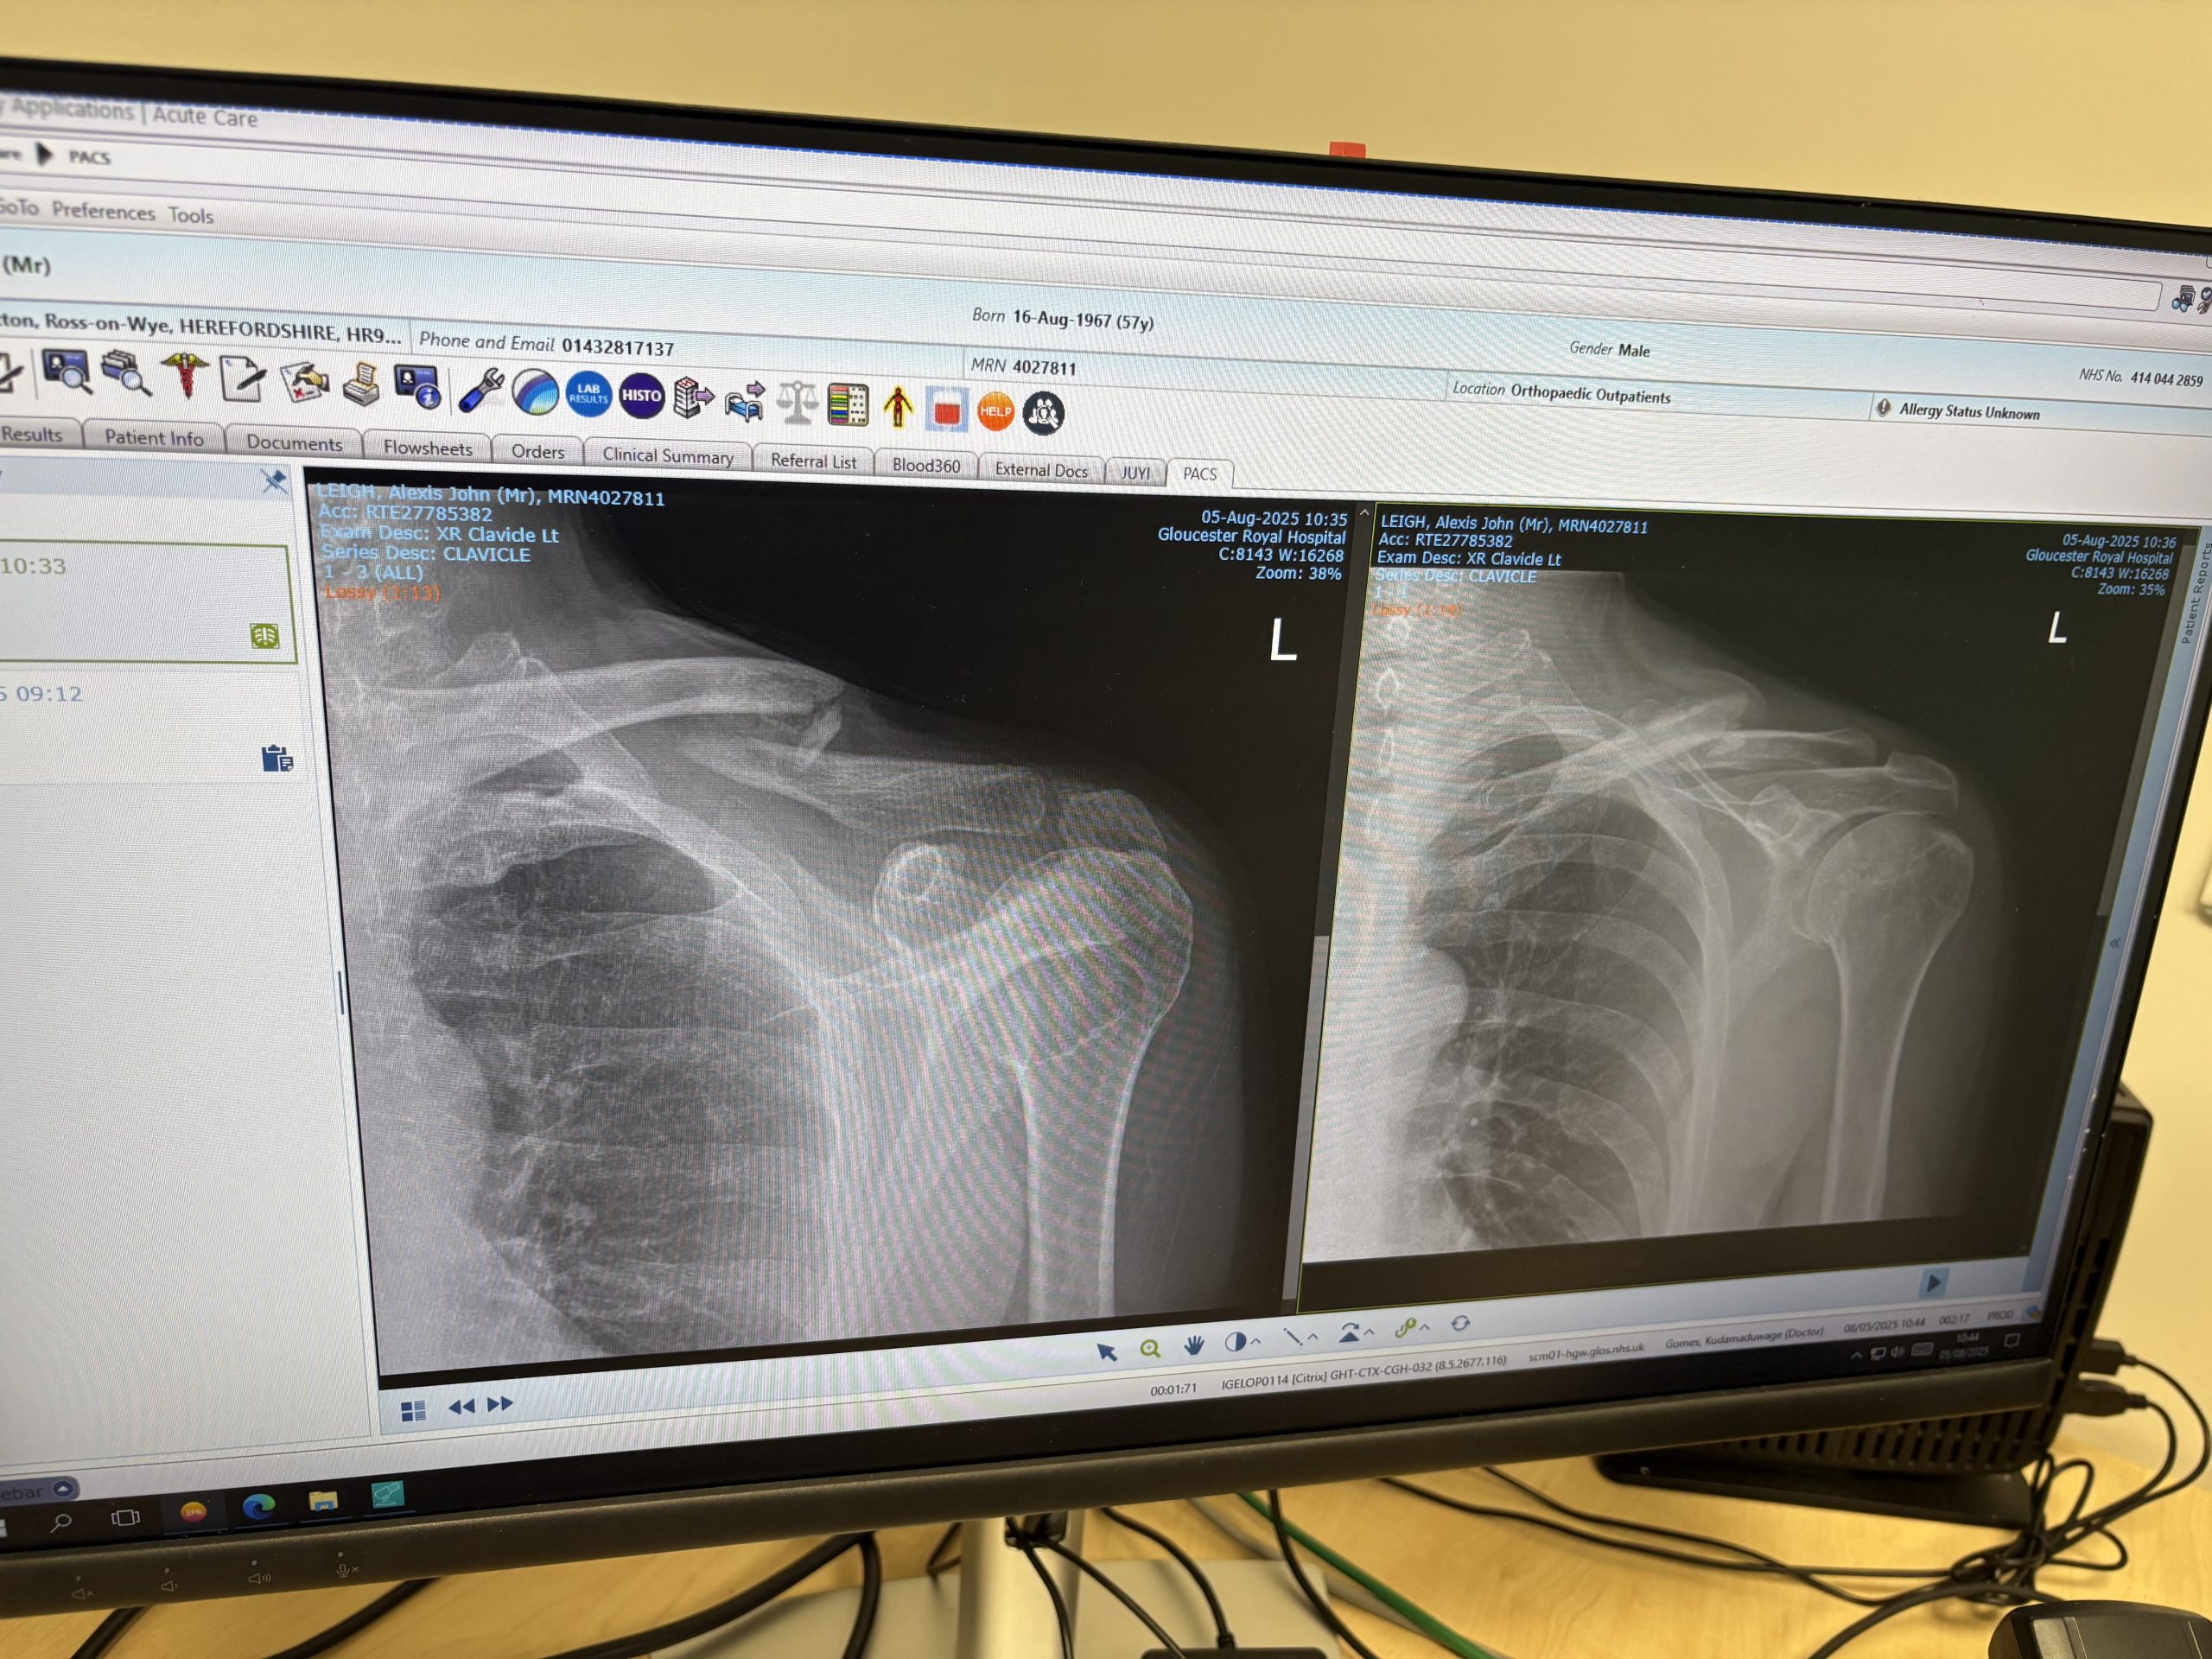

On the left is Splatterday+6 weeks, the right an update a couple of weeks ago. You don’t need to look too closely as I’ve totally been there. Summary is there’s lots of lovely new bone pulling the break together, but it’s on the light side of hard. “Can I got mountain biking?” I asked the consultant keen to fob me off by offering not much beyond the ‘don’t sue us script‘ – Pause. Push glasses up nose. Refer to notes clearly checking age. “Well I wouldn’t recommend it, but if you ride you absolutely cannot crash”